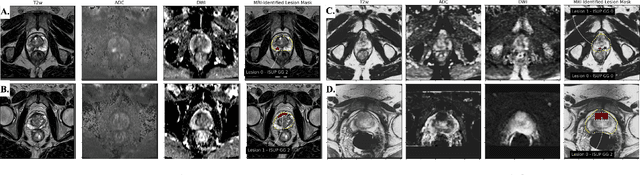

Abstract:Non-invasive prostate cancer detection from MRI has the potential to revolutionize patient care by providing early detection of clinically-significant disease (ISUP grade group >= 2), but has thus far shown limited positive predictive value. To address this, we present an MRI-based deep learning method for predicting clinically significant prostate cancer applicable to a patient population with subsequent ground truth biopsy results ranging from benign pathology to ISUP grade group~5. Specifically, we demonstrate that mixed supervision via diverse histopathological ground truth improves classification performance despite the cost of reduced concordance with image-based segmentation. That is, where prior approaches have utilized pathology results as ground truth derived from targeted biopsies and whole-mount prostatectomy to strongly supervise the localization of clinically significant cancer, our approach also utilizes weak supervision signals extracted from nontargeted systematic biopsies with regional localization to improve overall performance. Our key innovation is performing regression by distribution rather than simply by value, enabling use of additional pathology findings traditionally ignored by deep learning strategies. We evaluated our model on a dataset of 973 (testing n=160) multi-parametric prostate MRI exams collected at UCSF from 2015-2018 followed by MRI/ultrasound fusion (targeted) biopsy and systematic (nontargeted) biopsy of the prostate gland, demonstrating that deep networks trained with mixed supervision of histopathology can significantly exceed the performance of the Prostate Imaging-Reporting and Data System (PI-RADS) clinical standard for prostate MRI interpretation.

Abstract:Early prostate cancer detection and staging from MRI are extremely challenging tasks for both radiologists and deep learning algorithms, but the potential to learn from large and diverse datasets remains a promising avenue to increase their generalization capability both within- and across clinics. To enable this for prototype-stage algorithms, where the majority of existing research remains, in this paper we introduce a flexible federated learning framework for cross-site training, validation, and evaluation of deep prostate cancer detection algorithms. Our approach utilizes an abstracted representation of the model architecture and data, which allows unpolished prototype deep learning models to be trained without modification using the NVFlare federated learning framework. Our results show increases in prostate cancer detection and classification accuracy using a specialized neural network model and diverse prostate biopsy data collected at two University of California research hospitals, demonstrating the efficacy of our approach in adapting to different datasets and improving MR-biomarker discovery. We open-source our FLtools system, which can be easily adapted to other deep learning projects for medical imaging.